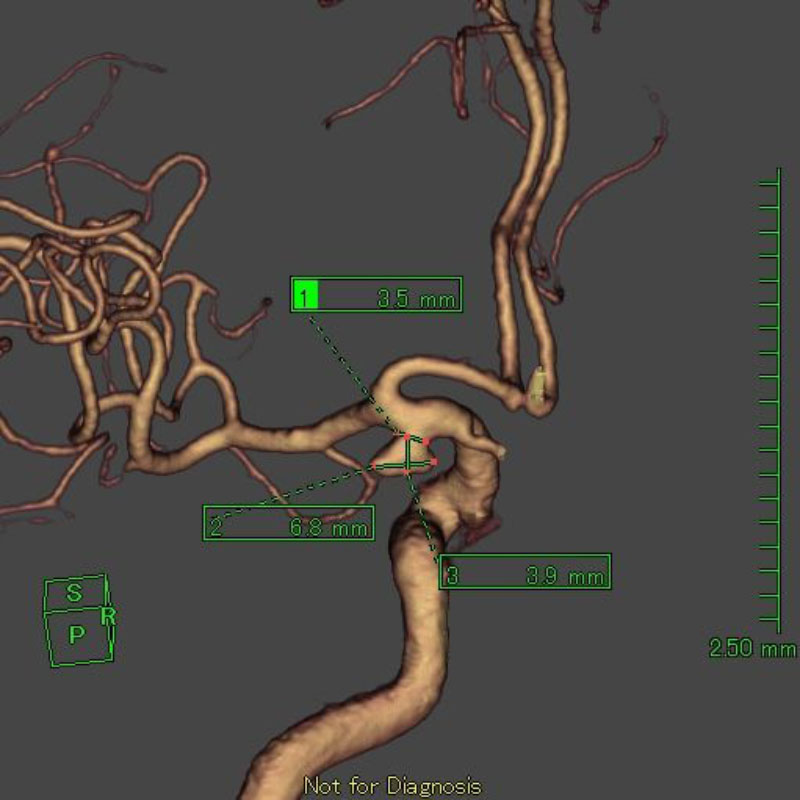

20

'26年4月

80代

右中大脳動脈瘤

クリッピング術

手術前

クリップ前

クリップ後

術後血管撮影